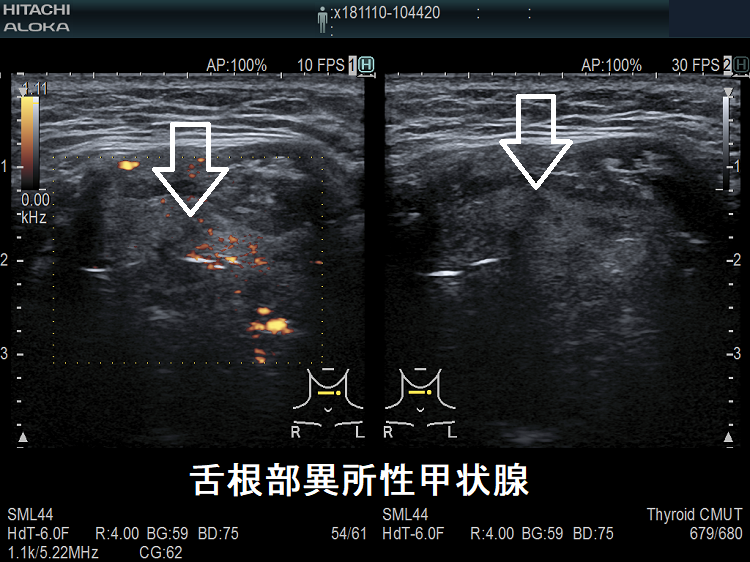

舌根部異所性甲状腺 超音波(エコー)画像

舌根部異所性甲状腺(正位置には無し)

舌根部異所性甲状腺 ドプラーモード

舌根部異所性甲状腺 ドプラーモード;有意な内部血流を認めません。